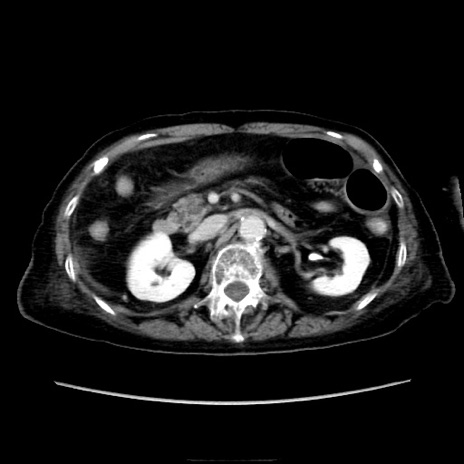

症例40(横断像)

【症例】90歳代女性

【主訴】腹痛・嘔吐

【現病歴】 食欲低下、嘔吐があり昨日他院受診。肺炎と診断され入院となる。入院後より腹部全体に圧痛あり。胃管留置され経過みていたが、症状持続するため、

当院転院となる。

【既往歴】胸椎圧迫骨折、胆石症

【身体所見】腹部:中央に激痛あり、圧痛あり、反跳痛不明

【データ】WBC 17100、CRP 18.82

横断像